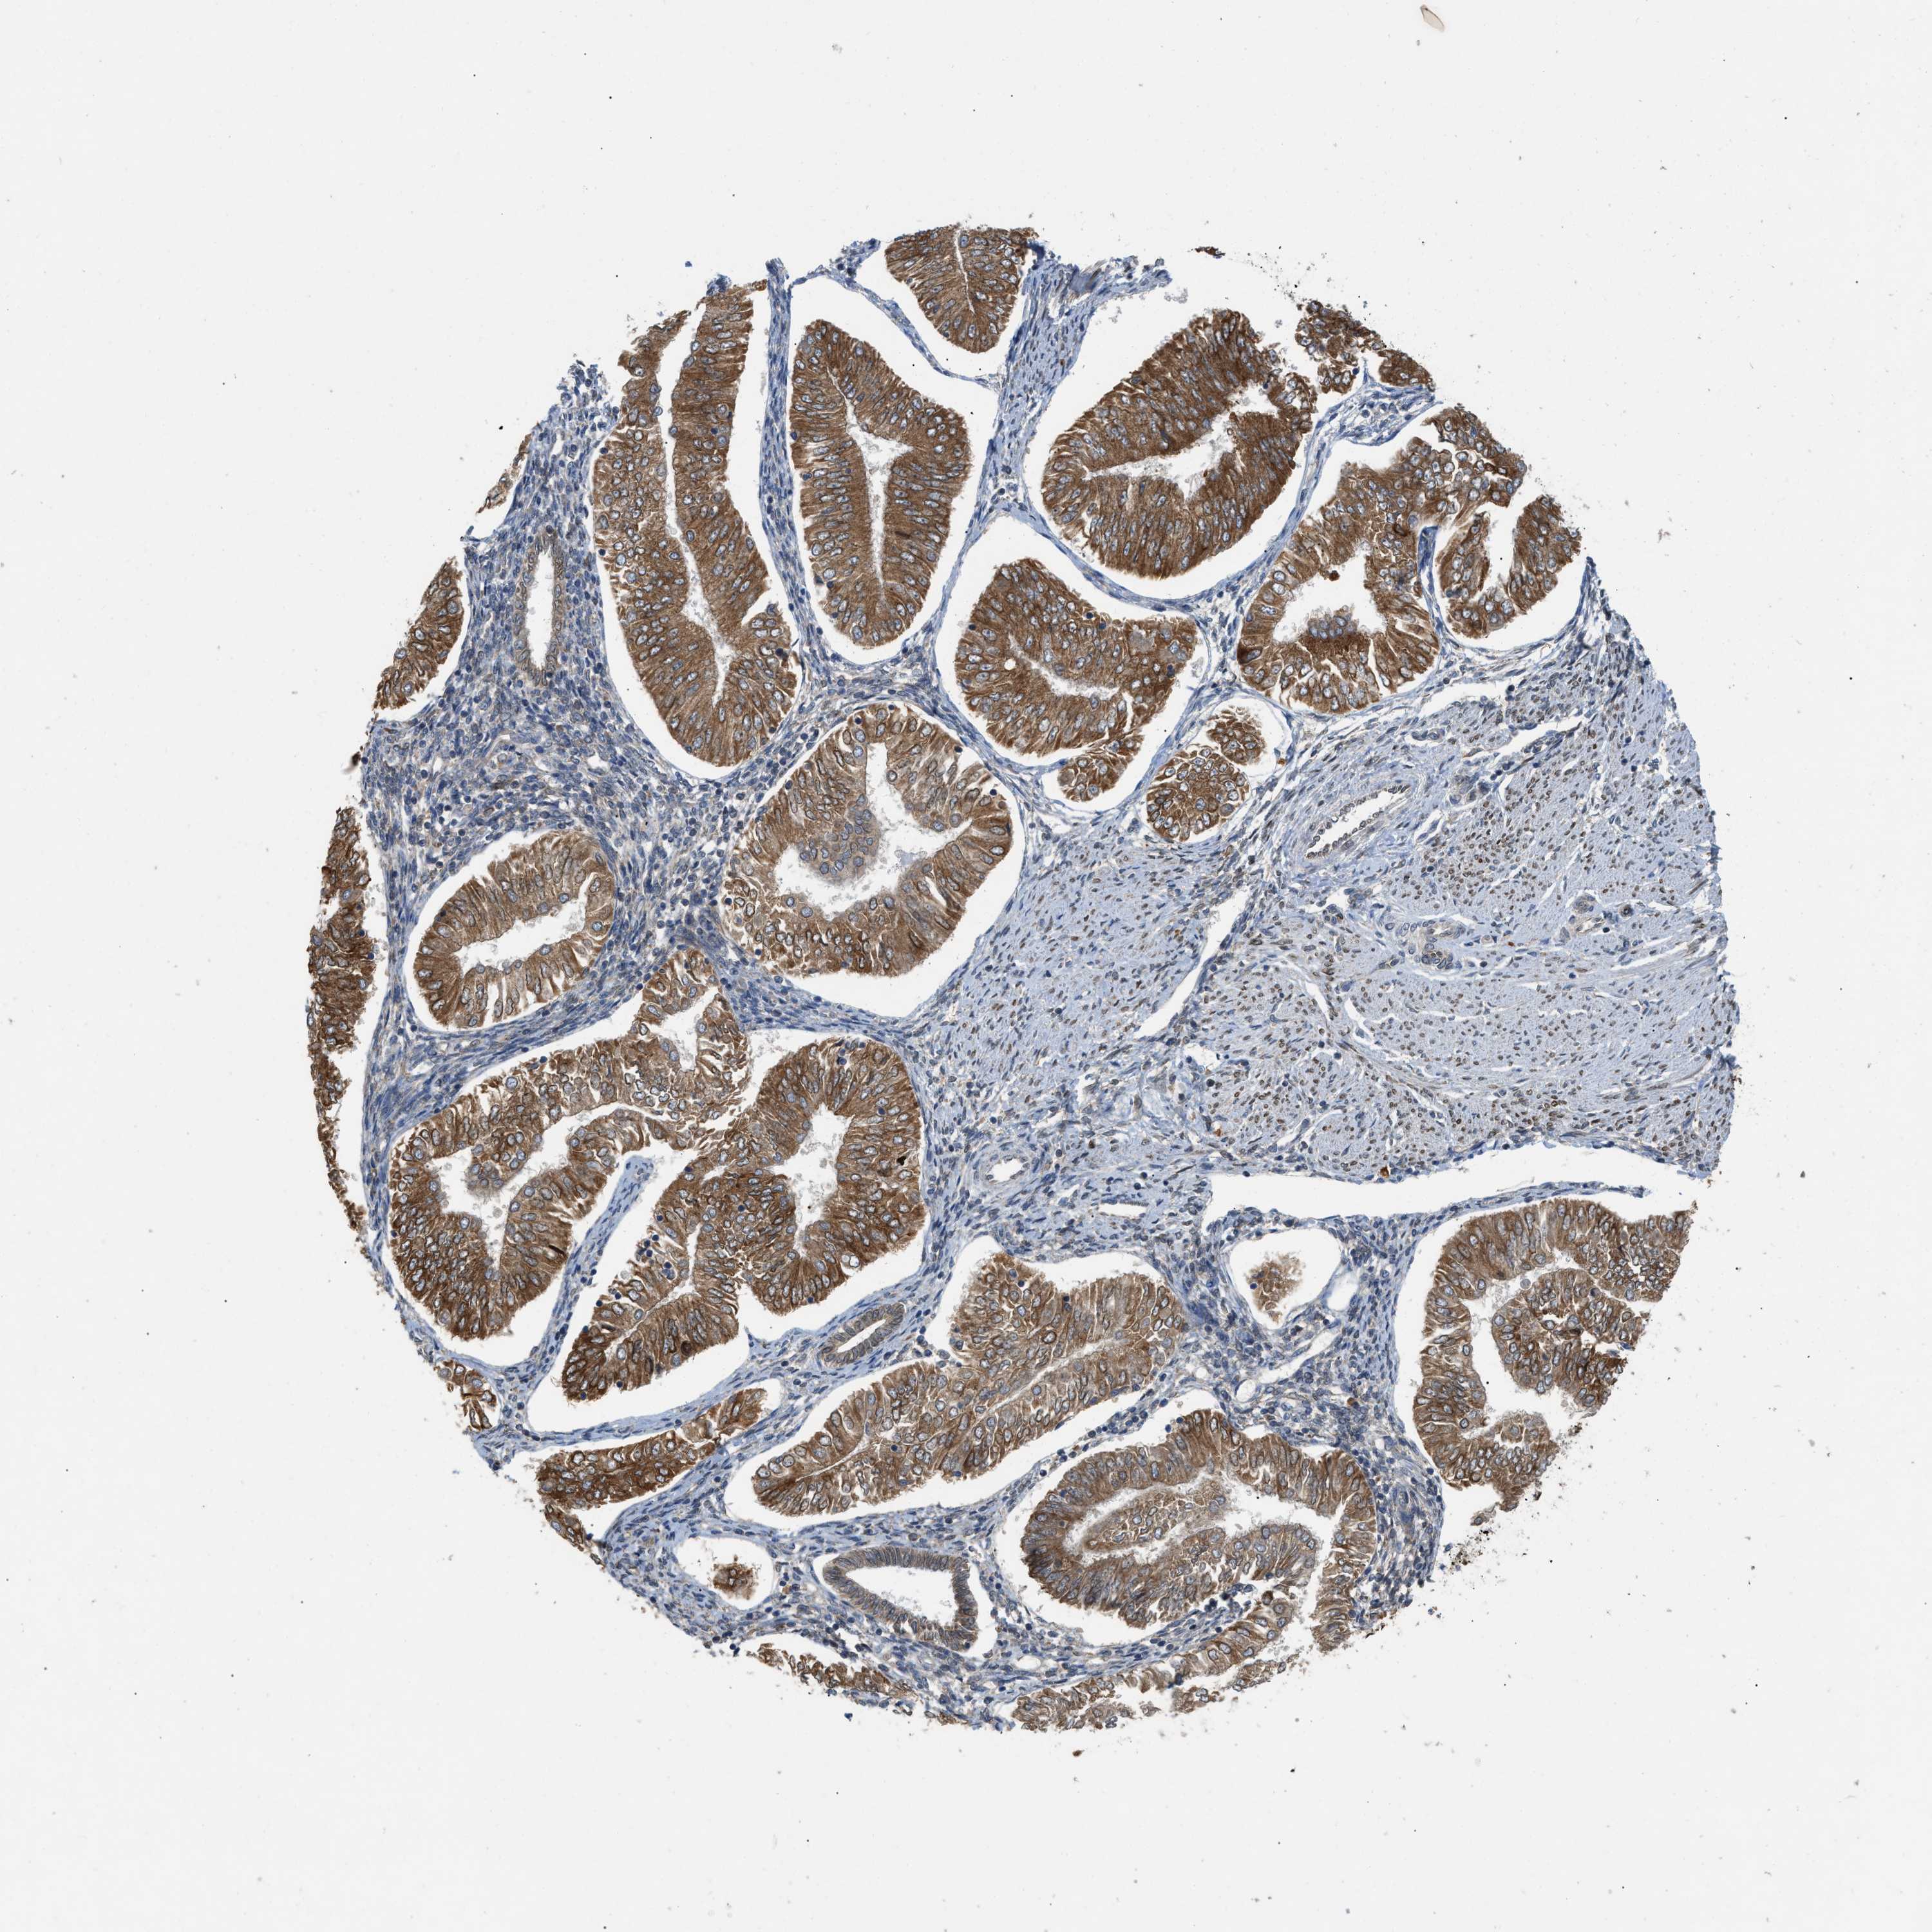

ENDOMETRIAL CANCER - Protein expressioni

A mouse-over function shows sample information and annotation data. Click on an image to view it in a full screen mode. Samples can be filtered based on level of antibody staining by selecting one or several of the following categories: high, medium, low and not detected. The assay and annotation is described here.

Note that samples used for immunohistochemistry by the Human Protein Atlas do not correspond to samples in the TCGA dataset.

Antibody stainingi

Antibody staining in the annotated cell types in the current human tissue is reported as not detected, low, medium, or high, based on conventional immunohistochemistry profiling in selected tissues. This score is based on the combination of the staining intensity and fraction of stained cells.

Each image is clickable and will lead to virtual microscopy that enables deeper exploration of all samples and also displays staining intensity scores, fraction scores and subcellular localization as well as patient and tissue information for each sample.

Antibody HPA014394

Staining

High

Medium

Low

Not detected

Intensity

Strong

Moderate

Weak

Negative

Quantity

>75%

75%-25%

<25%

None

Location

Nuclear

Cytoplasmic/membranous

Cytoplasmic/membranous,nuclear

Adenocarcinoma, NOS